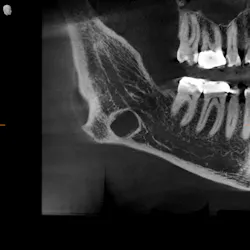

As part of our intake process to make a sleep mandibular advancement device, we take a cone beam image (figures 1–4). This way we can evaluate sinuses, septum, turbinates, teeth, and jaws.

Upon examination, it was noted that a dark, radiolucent lesion was present on the lower right jaw, anterior to the angle of the mandible. The patient didn’t have any pain, symptoms, or knowledge of the lesion. It was not palpable. He reported that he had his third molars removed in his twenties with no complications.

Reflecting back on my amazing pathology education at Creighton University (thanks, Dr. Bob Achterberg!), I immediately tried to think of what my differentials could be. Full disclosure: I was worried that my patient’s jaw could break at any moment. I thought it was a residual cyst from third-molar removal.

The Stafne defect is code for a depression in the bone, a concavity, due to the submandibular gland. In addition, it can’t be qualified as a cyst because there is no epithelial lining or fluid content. It does usually occur more in men as well.1 There is no treatment necessary; it’s something we can just monitor.